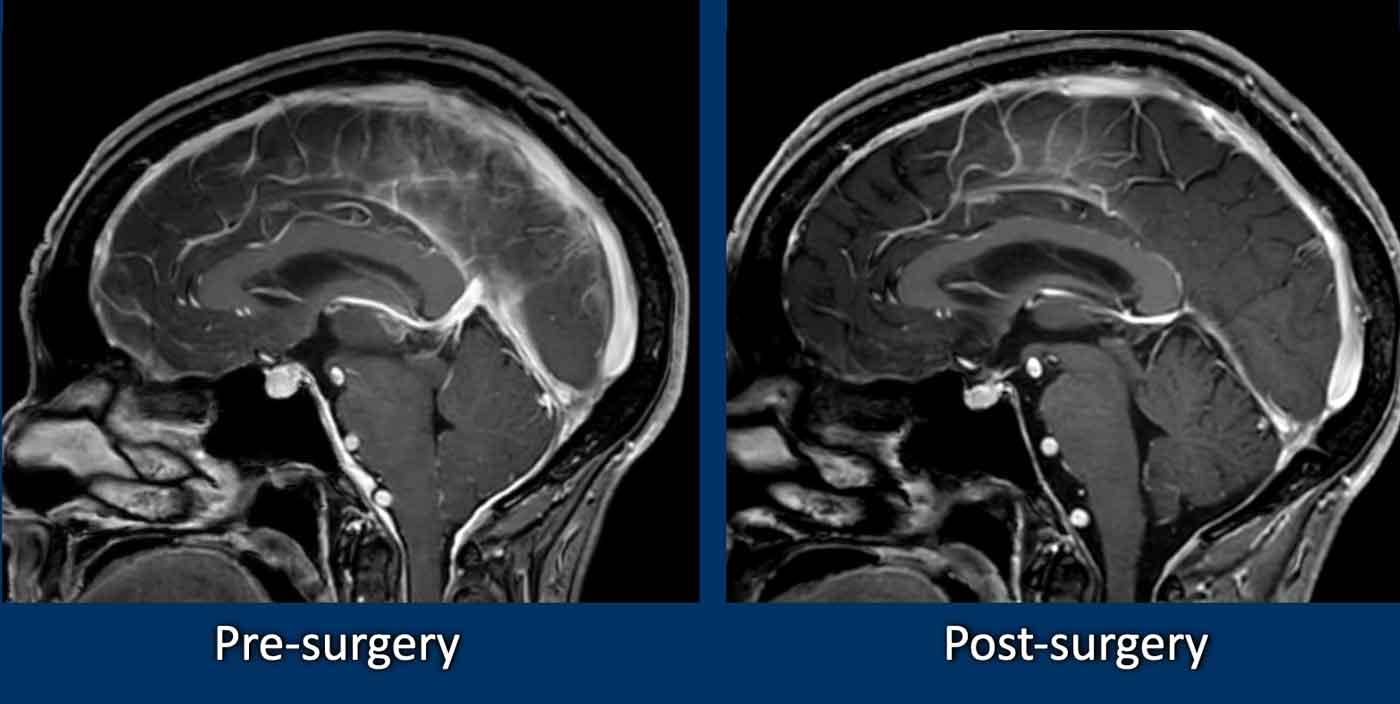

SIH và Dị dạng Chiari type I

Mặc dù SIH và dị dạng Chiari type I (CM1) là hai bệnh lý hoàn toàn khác nhau, cả hai đều có thể biểu hiện với đau đầu mạn tính và hạnh nhân tiểu não tụt thấp.

Ở bệnh nhân SIH, điều này có thể dẫn đến chẩn đoán nhầm thành CM1.

Hãy nghiên cứu các hình ảnh trước.

Cả hai bệnh nhân đều là phụ nữ trẻ với đau đầu mạn tính.

Bệnh nhân nào mắc SIH và bệnh nhân nào mắc CM1?

Hình ảnh

- Hạnh nhân tiểu não tụt thấp

Dấu hiệu không thật sự rõ ràng, một phần do có xảo ảnh chuyển động, nhưng hình dạng thân não không bình thường và có vẻ khoảng cách giữa cầu não và thể vú bị rút ngắn.

Có thể cũng có một số dấu hiệu ứ trệ tĩnh mạch. - Ngoài hạnh nhân tiểu não tụt thấp, hình ảnh trông bình thường.

Tiếp tục với các hình ảnh bổ sung……

- Bốn hình ảnh bên trái cho thấy các dấu hiệu điển hình của SIH với bờ lồi của xoang ngang, khoảng cách ngắn giữa thể vú và cầu não, và hình ảnh trung não bị võng xuống.

- Các hình ảnh bên phải không cho thấy các dấu hiệu này.

Bệnh nhân SIH đã được điều trị bốn lần bằng vá máu mù và đạt kết quả thành công.

Bệnh nhân Chiari type I đã được phẫu thuật giải ép vùng sọ-cổ và đạt kết quả tốt.

Đây là trách nhiệm của chúng ta với tư cách là bác sĩ chẩn đoán hình ảnh: giúp bệnh nhân SIH tránh khỏi việc bị điều trị nhầm như bệnh nhân Chiari type I.